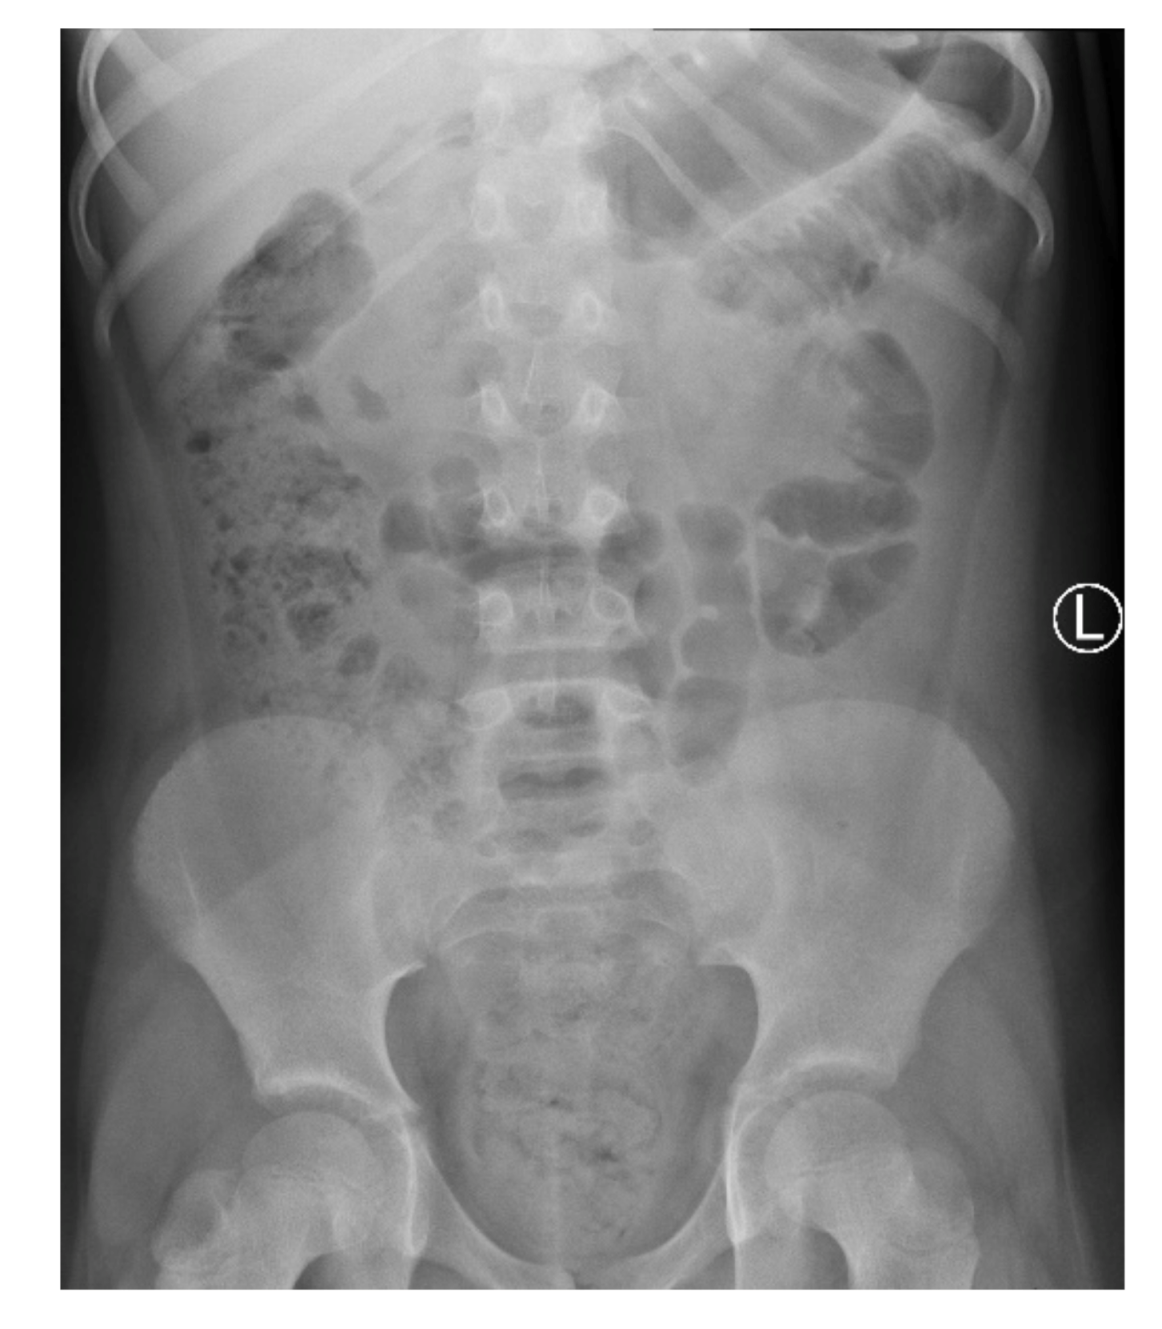

On admission, the patient presented with severe epigastric pain lasting for 3 days. In addition, the parents reported one episode of vomiting and stool retention lasting 2 days. The girl had no fever. On physical examination, the abdomen was distended. On palpation, significant pain, with increased tension of abdominal integuments in the right and central epigastrium, was observed. The lower quadrants of the abdomen were soft with mild tenderness, with palpable stool masses in the lower left iliac fossa. The percussion examination was impaired by the excess amount of subcutaneous tissue with tympanitic sounds in the epigastrium and slightly dull sounds over the left iliac region. Peristalsis was heard in the umbilical region. The pain intensified with changes in position. Diagnostics for acute abdominal diseases were implemented. The differential diagnosis included acute pancreatitis, gastrointestinal obstruction, gastrointestinal perforation (including duodenal perforation) and acute appendicitis. Laboratory tests showed elevated inflammatory parameters: CRP (C-reactive protein) at 69.42 mg/L, insignificant leukocytosis with a WBC (white blood cell count) of 10.65 thousand/μL, with a neutrophil predominance of 71%, and fibrinogen at 524.7 mg/dL; the serum amylase and lipase levels were within normal limits. As for imaging examinations, a plain abdominal X-ray was initially performed, which showed no signs of obstruction or perforation of the gastrointestinal tract but did show fecal masses in the ascending colon and rectum (Figure 1).

Figure 1. A plain X-ray of the abdominal cavity on admission: no signs of obstruction or perforation of the gastrointestinal tract and fecal masses in the large intestine.